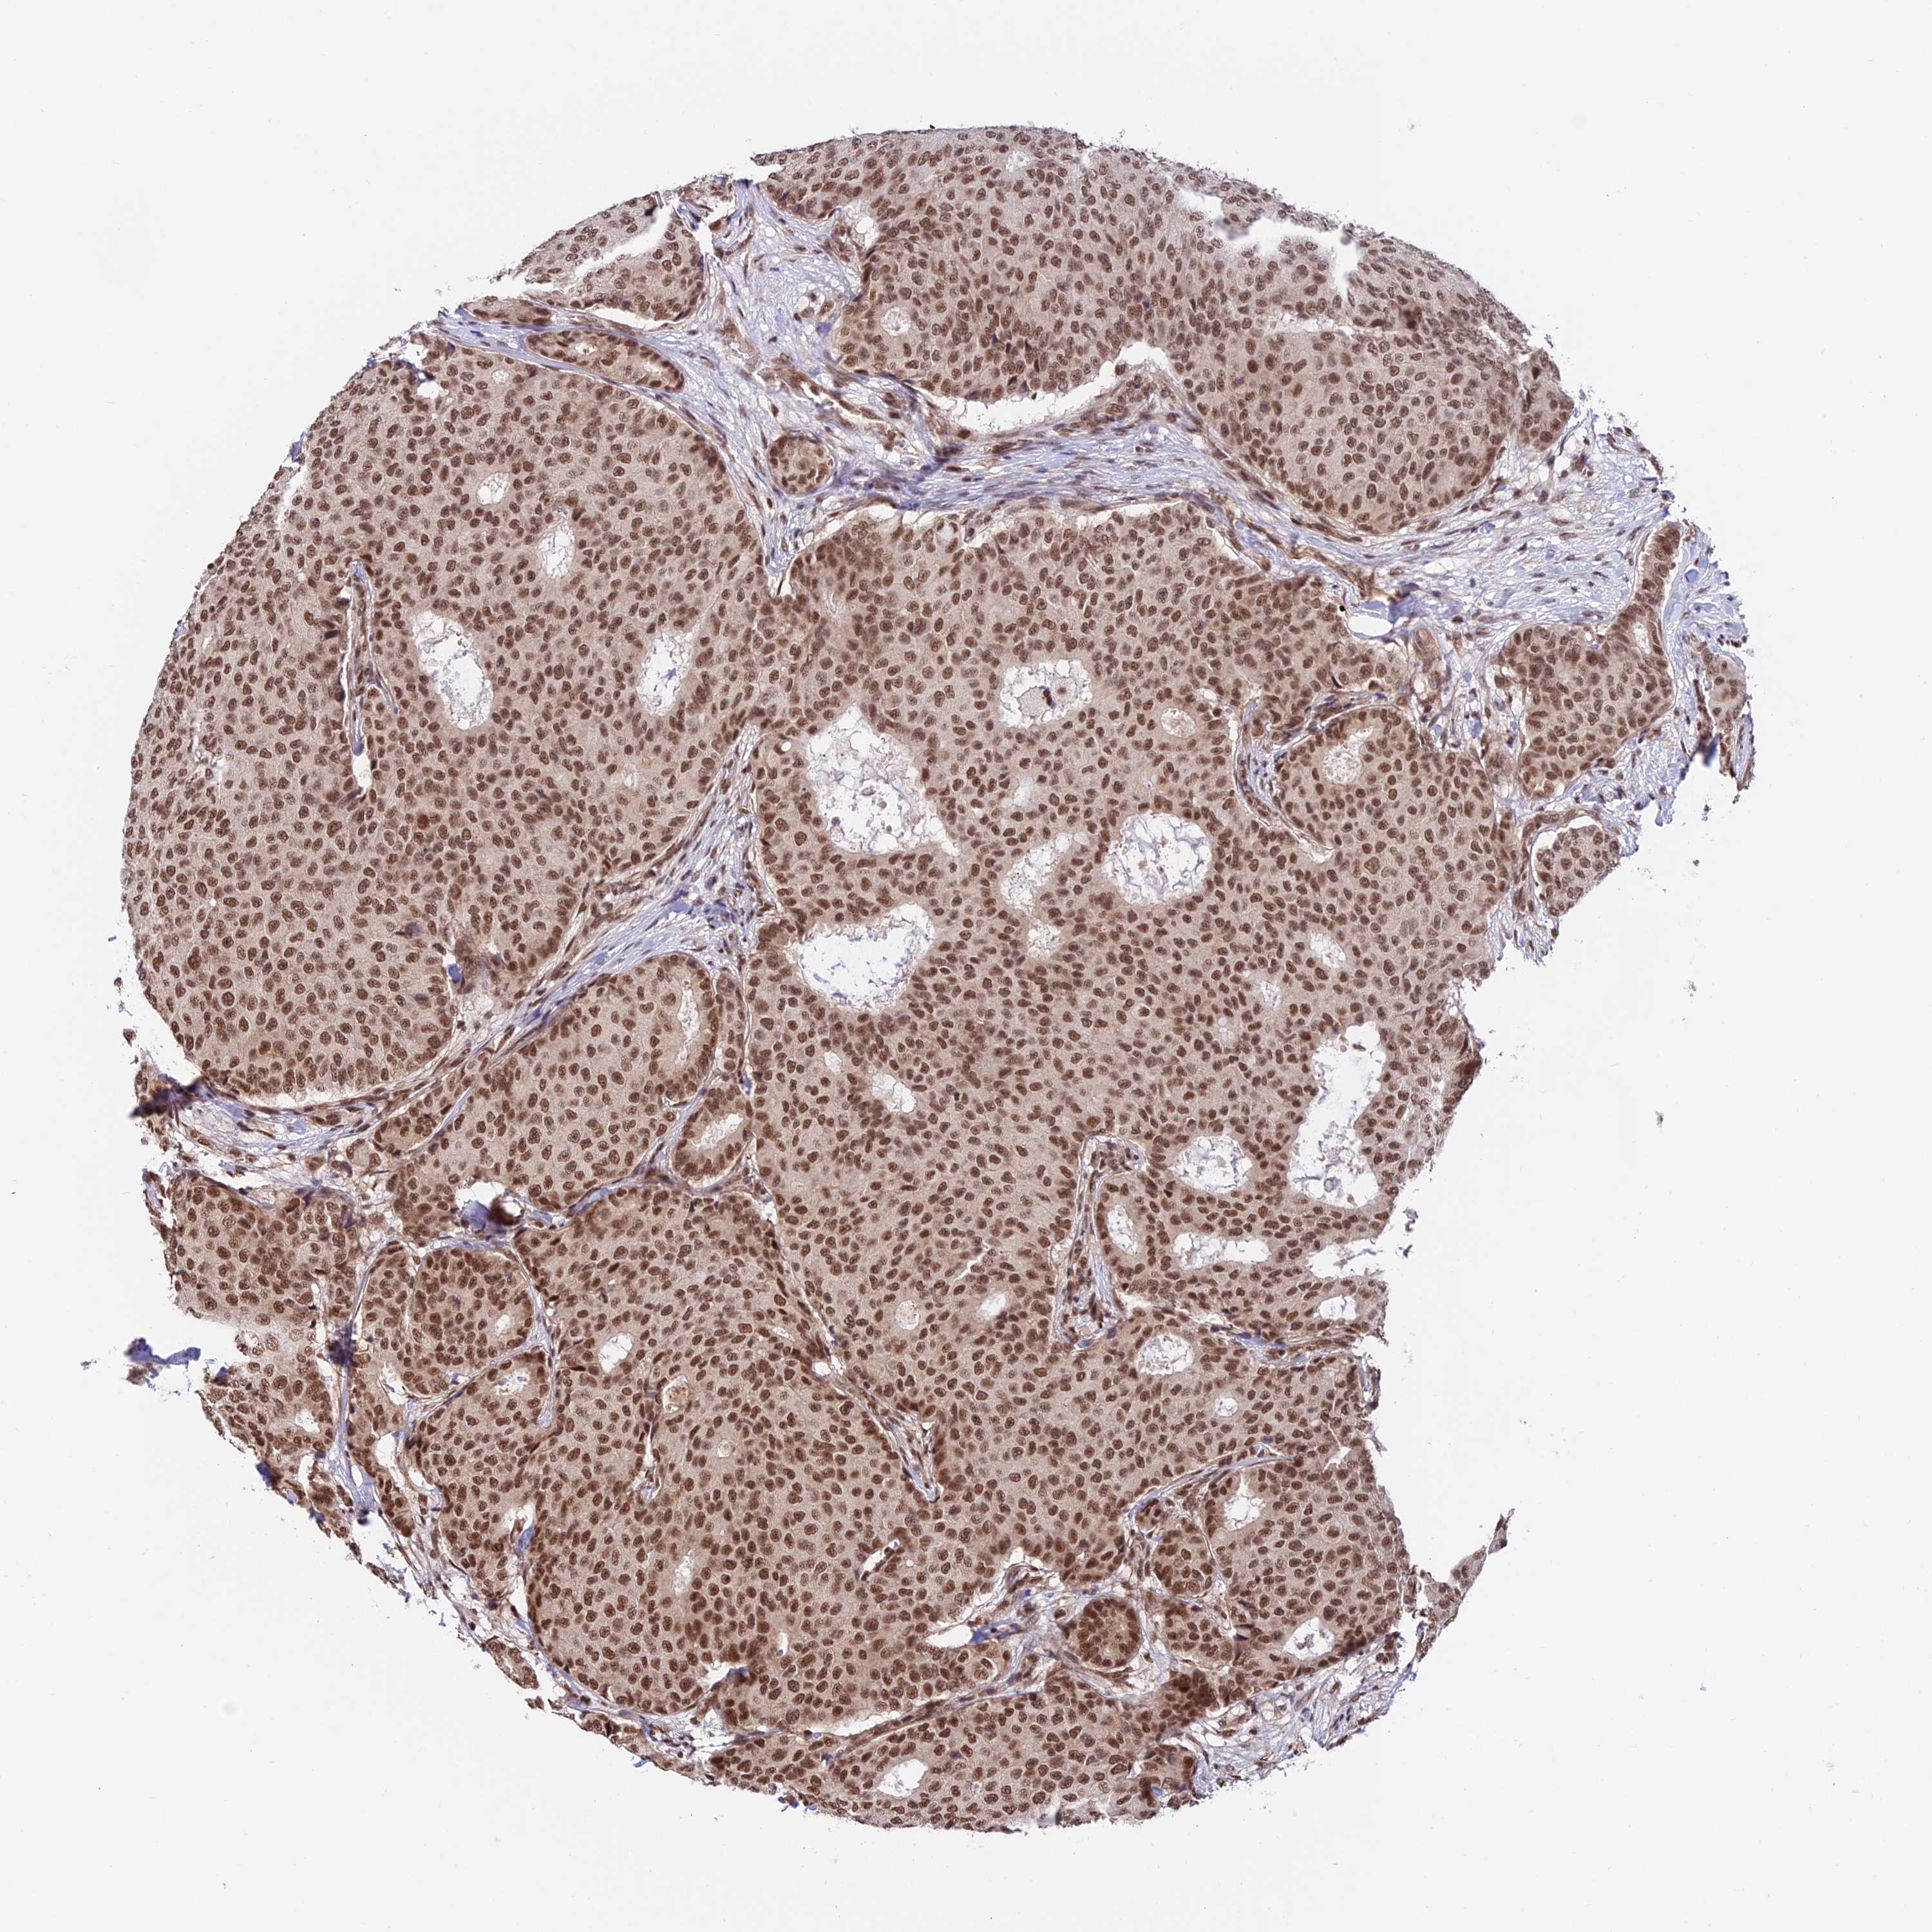

CANCER BREAST CANCER Show tissue menu

BRCA TCGA BRCA VALIDATION PROTEIN EXPRESSION

Breast cancer

Human cancer